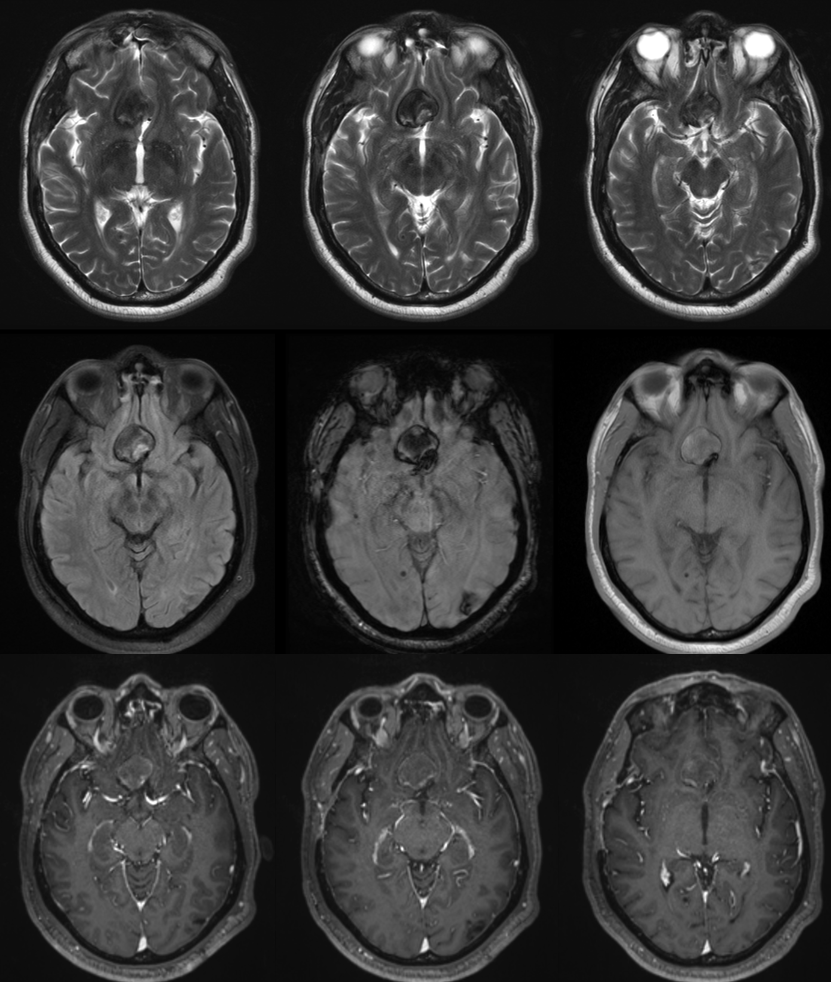

Giant ACOM

More problems? Yes

So far, we have a giant mostly thrombosed ACOM aneurysm with adjacent edema, a chronically occluded right cervical ICA, and right ACA dependent on the ACOM flow… Not easy

Spins are good

A secondary reconstruction and detailed analysis is better. What does arrow point to?